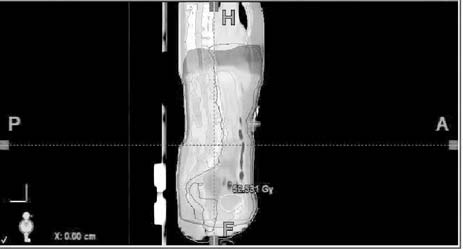

Obr. č. 1: Distribuce izodóz při abdominopelvickém

ozáření - technice „open field" v rovině transverzální, při

frontální a sagitální rekonstrukci, 3D